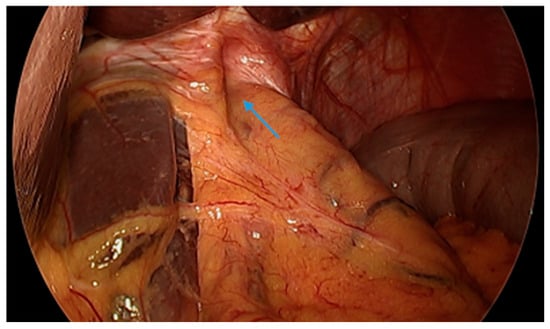

Magnetic sphincter augmentation (MSA) devices, such as the LINX© system, have also been used as an experimental approach to mitigate post-SG GERD. MSA devices utilize titanium beads with a magnetic core connected with titanium wires to form a ring shape, which is laparoscopically placed around the lower esophageal sphincter as a reinforcement (Figure 9 and Figure 10). Some studies have revealed favorable results [96,97,98,99,100]. A meta-analysis of three studies with a total of 33 patients revealed a pooled mean difference between preoperative and postoperative GERD-Heath-Related Quality of Life Questionnaire (GERD-HRQL) scores to be 17.5 following MSA [101]. However, data are limited. Further studies are warranted to establish the safety and efficacy of MSA devices following SG.

Figure 9.

Laparoscopic image reveals a patient post-sleeve gastrectomy with a defect in the diaphragmatic hiatus (arrow) and subsequent gastroesophageal reflux disease. Image courtesy of Dr. Brian Louie, Chief of Thoracic Surgery at Swedish Medical Center in Seattle, Washington, USA.